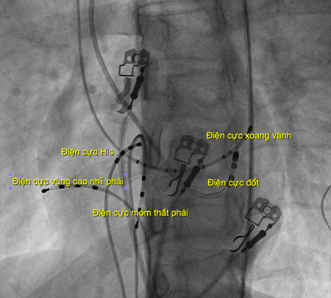

Hình 1: Các điện cực trong buồng tim, nghiêng trái 30